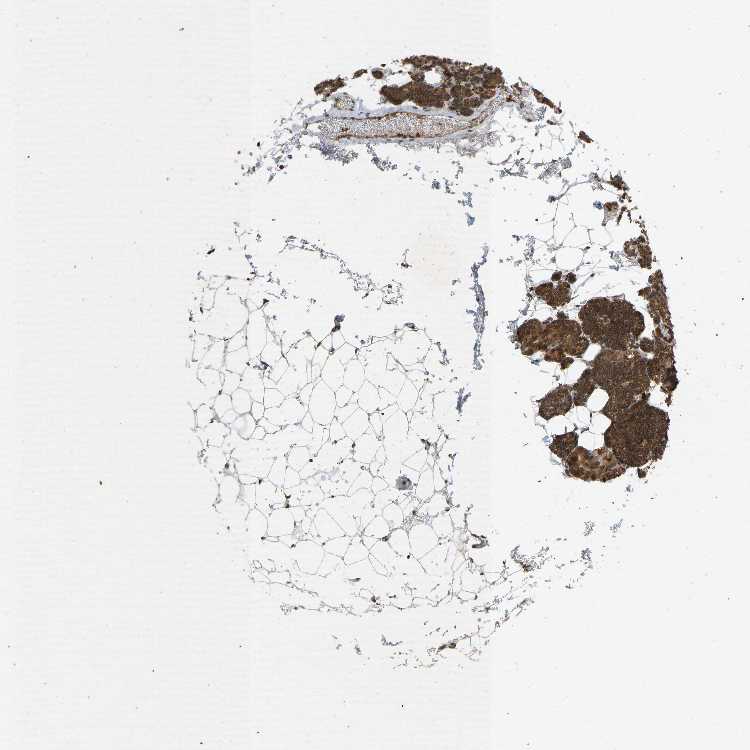

PARATHYROID GLAND - Antibody stainingi

Antibody staining in the annotated cell types in the current human tissue is reported as not detected, low, medium, or high, based on conventional immunohistochemistry profiling in selected tissues. This score is based on the combination of the staining intensity and fraction of stained cells.

Each image is clickable and will lead to virtual microscopy that enables deeper exploration of all samples and also displays staining intensity scores, fraction scores and subcellular localization as well as patient and tissue information for each sample.

Antibody HPA008297Antibody HPA025922Antibody CAB019277

Glandular cells MediumMediumHigh